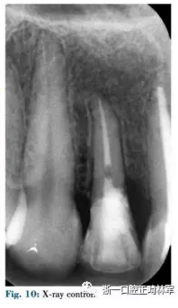

正畸牽引結(jié)束(圖7)時(shí),皮瓣抬高后使用橡皮障暴露邊緣(圖8),進(jìn)行纖維樁修復(fù),堆好核后使用層壓瓷貼面修復(fù)(圖9-11)。